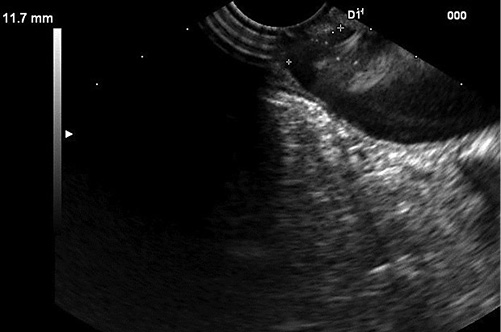

A presumptive diagnosis of disconnected MPD with a gastric fistula due to previous cystic drainage was made, but endoscopic ultrasound (EUS) was performed to exclude a main-duct intraductal papillary mucinous neoplasm (MD-IPMN). Endoscopically, a fistulous orifice 10 mm wide in the gastric antrum was apparent (Fig. 1), with a gelatinous, high-viscosity content which could not be removed despite vigorous lavage. A gastroscope was used to intubate the fistulous tract, but progression was not possible due to the viscous content. The EUS showed a globally dilated MPD (40 mm in the body) with a loss of interface with the gastric wall in the isthmus, 10 mm in diameter (Fig. 2). Fine-needle aspiration (FNA) of the MPD with a 19-gauge needle was performed, revealing a very thick mucinous content. Cytologic analysis confirmed high-grade IPMN, and the patient was referred to surgery (Fig. 3).